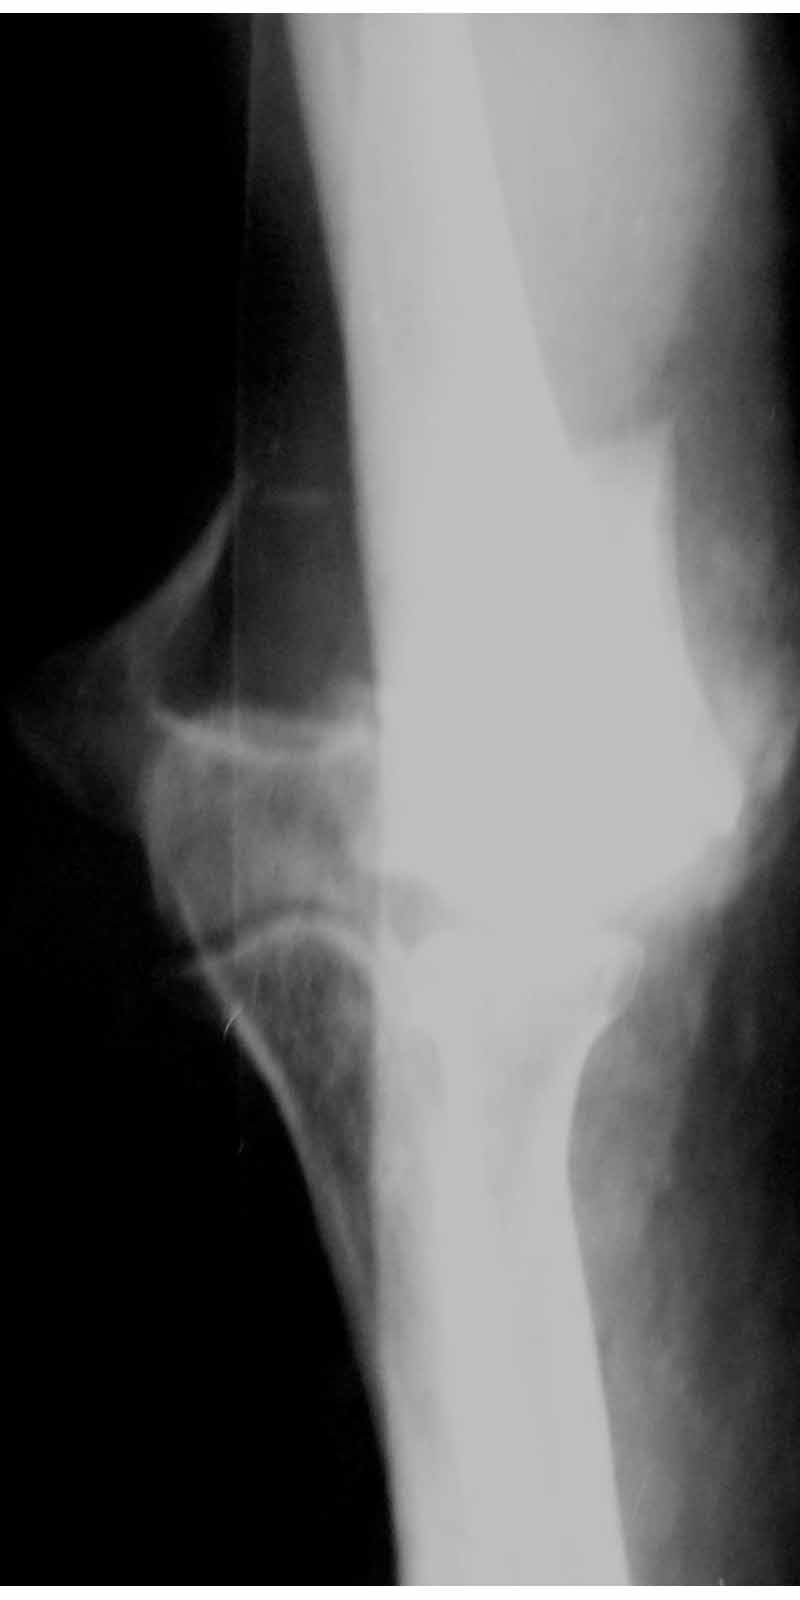

Уважаемые коллеги! Мужчина, 28 лет. 1 сутки назад получил бытовую травму - закрытый чрезмыщелковый перелом правой плечевой кости со смещением. По месту жительства в ЦРБ - репозиция, иммобилизация. Направлен к нам.

Место болезни без особенностей, неврологических и сосудистых расстройств нет. Принято решение об оперативном лечении - чрескостный остеосинтез.Предложения по конструкции АВФ (т.к. мнения расходятся)? Заранее благодарю! С уважением,А.В.ВладзимирскийДонецкий НИИ травматологии и ортопедииДонецк, Украина